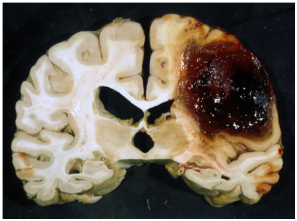

Hemorrhagic stroke

Occurs when a small blood vessel in the brain becomes weak and ruptures. It includes bleeding around brain and bleeding into brain. Based on the manifestations and causes there 3 types of hemorrhagic stroke. Subarachnoid hemorrhage (SAH), intracerebral hemorrhage (ICH) and subdural hematomas.